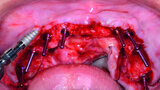

Fig 13 Arcade mandibulaire anesthésiée

Fig 14 Guide chirurgical mandibulaire stabilisé

Fig 15 Implants et coiffes de cicatrisation entourés du matériel de greffe